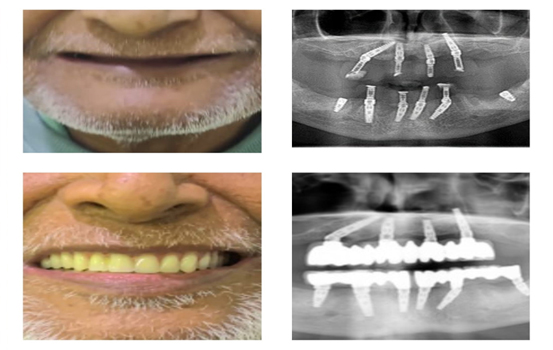

ALL ON 4 AND ALL ON 6 DENTAL IMPLANTS

ALL ON 4 DENTAL IMPLANTS.

When patients have a healthy jawbone and supportive gums, the success rate of dental implants is significantly higher.

However, in some cases, patients may present with less ideal conditions for implant placement, such as insufficient bone volume, particularly in the posterior regions of the upper or lower jaw. In such scenarios, where extensive grafting procedures are to be avoided, the “All-on-Four” treatment often becomes the preferred option for replacing missing teeth.

The All-on-Four method boasts a high success rate and allows for the placement of approximately 12 teeth supported by just four implants. The feasibility and success of this treatment depend on the condition of the bone and the patient’s overall health.

However, in some cases, patients may present with less ideal conditions for implant placement, such as insufficient bone volume, particularly in the posterior regions of the upper or lower jaw. In such scenarios, where extensive grafting procedures are to be avoided, the “All-on-Four” treatment often becomes the preferred option for replacing missing teeth.

The All-on-Four method boasts a high success rate and allows for the placement of approximately 12 teeth supported by just four implants. The feasibility and success of this treatment depend on the condition of the bone and the patient’s overall health.

ALL ON 6 DENTAL IMPLANTS

This technique is widely used in full-mouth rehabilitation, providing patients with exceptional comfort throughout the treatment process.

In cases where no teeth are present in both the upper and lower arches, and if X-rays reveal adequate bone support and healthy gums, dentists typically opt for the All-on-Six approach. This involves placing six implants in both the upper and lower arches of the jaw.

After successful bone integration, up to 14 teeth can be supported by the six implants in each arch, depending on the patient’s overall health condition.

Both the All-on-Four and All-on-Six dental implant procedures offer significant benefits, including comfort, minimal invasiveness, reduced treatment time, and high effectiveness. These procedures are generally performed under local anesthesia.